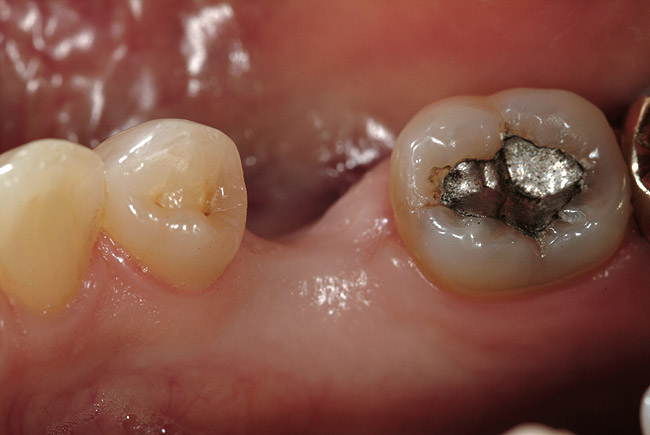

When fiber-reinforcing materials were introduced, the focus for their use was for periodontal splinting and stabilization resulting from tooth mobility.6,10,16,41-43 There is no doubt that splinting does reduce tooth mobility while the splint is in place.44 In the last decade, research supports the use of periodontal splinting as recommended therapy to stabilize those teeth to improve long-term prognosis.45-47 In a long-term clinical evaluation of splinting over a period of 48 to 96 months, using the original Ribbond Reinforcement Ribbon in fiber-reinforced composite resins was highly successful.17 The success of these splints can be attributed to close adaptation of the fiber ribbon to the tooth surface combined with cross stabilization of the mobile teeth by placing adhesive composite resin on the facial surfaces (Figure 4A, Figure 4B, Figure 4C, Figure 4D, Figure 4E).34,35 Splinting of traumatized teeth with fiber-reinforcing materials and adhesive composite resin has also been reported.48,49 When using fiber to stabilize the traumatized tooth or teeth or for tooth stabilization after re-implantation, the tooth must be allowed to have some movement and not be fixed in place.50,51

In vitro studies have demonstrated that the use of unidirectional glass-fiber reinforcement in the connector areas of FPDs contributes to significant composite reinforcement.29,36-38,66-68 Similar findings have been reported with a leno-weave UHMWPE and triaxial weave UHMWPE fiber.20,33,36 Fiber-reinforcing materials used by a dental laboratory are either resin pre-impregnated glass fibers, pre-polymerized composite resin surrounding glass fibers, biaxial braid UHMWPE, leno-weave UHMWPE, or a triaxial weave UHMWPE (Table 3). Typically, the preparation designs for the abutment teeth are inlay or onlay preparations (Figure 6A, Figure 6B, Figure 6C, Figure 6D). They are highly successful and can provide the patient with clinical service for more than 5 to 10 years.69 These restorations must be cemented using an adhesive resin technique with resin cements. Both etch-and-rinse adhesives with a self-cure or dual-cure composite resin cement or with a self-adhesive resin cement are indicated for cementing these restorations (Figure 7).36-38,70 Also, fiber-reinforcing materials are being used by dental laboratories in the fabrication of provisional restorations to reinforce and strengthen acrylic and composite-resin provisional materials.15,40,71